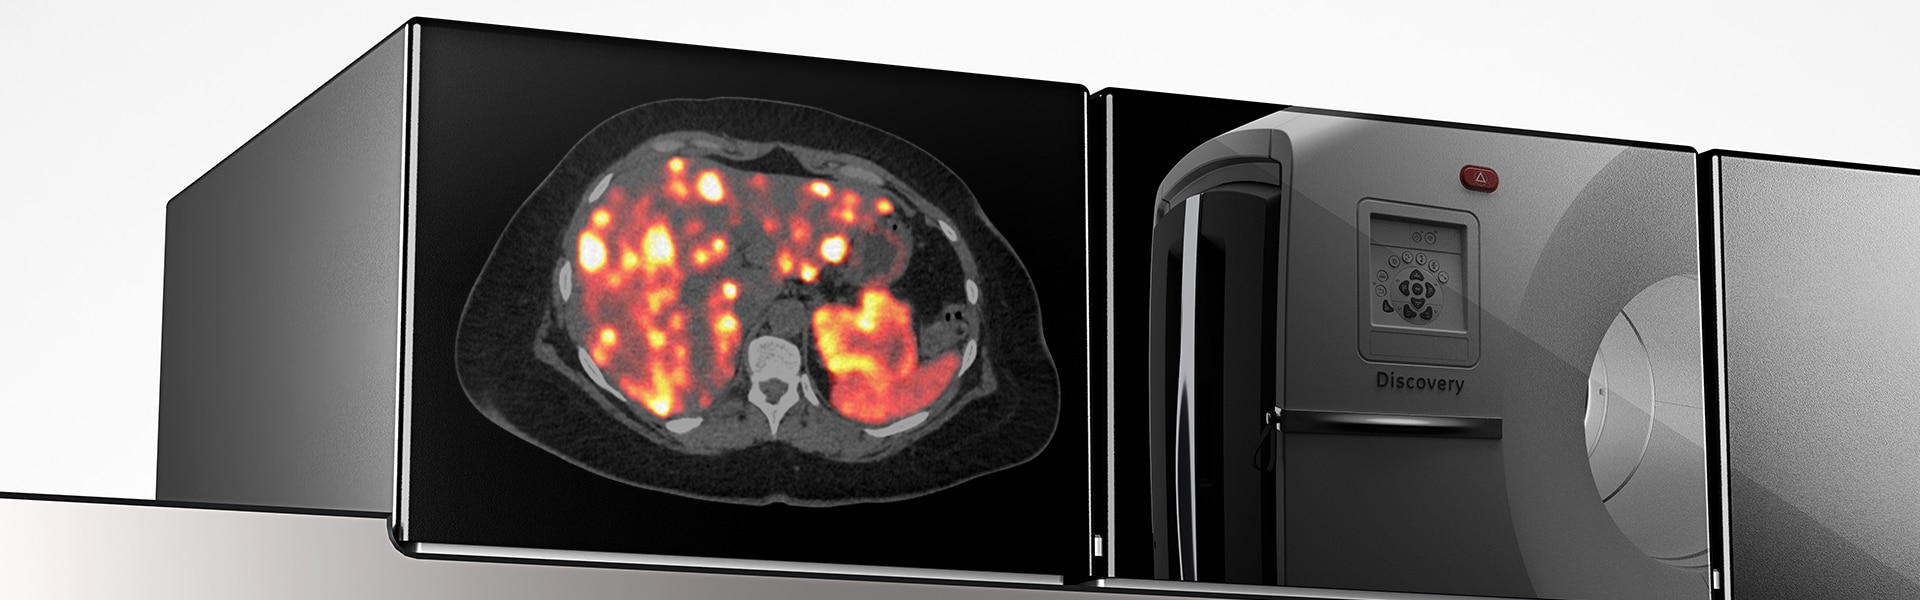

Discovery MI Gen 2 Overview

Detecção digital remasterizada

O Discovery MI Gen 2 foi projetado para oferecer

- Um campo de visão escalonável

- Um aumento de 50 por cento no pico NECR4

- Sensibilidade excepcional por cm (cps/kBq/cm)

- Uma redução de 33 por cento no tempo de varredura4

- Uma redução de 33 por cento na dose injetada4

O que mais um anel detector oferece a você? Muito.

Uma maneira totalmente nova de digitalizar1

- Melhoria de até 2x no SNR quando combinado com Q.Clear

- Complete 6 passagens com 5 camas por passagem em aproximadamente 20 minutos